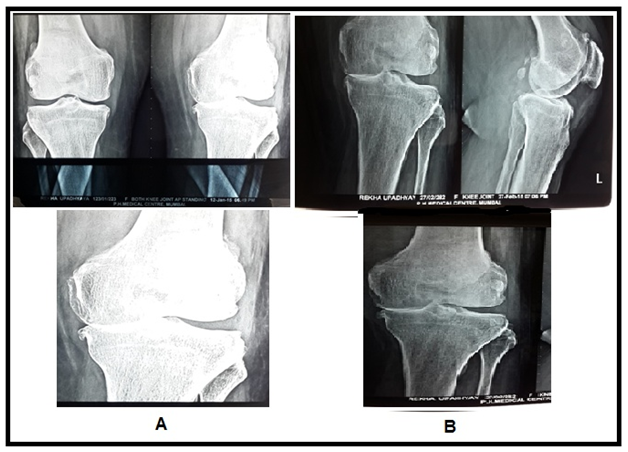

Figure 4 (A) MRI Images show subchondral cyst in femur with multiple breach in articular cartilage, (B) images show disappeared subchondral cyst with healed cartilage breach at one year follow up after stem cell transplantation.

Figure 7 X ray Images showing cartilage regeneration. (A) Image showing lost cartilage in medial joint space in left knee (B) image showing regenerated cartilage in the same joint.

The MRI study at the last follow−up visit (1 year) showed an important improvement in the cartilaginous tissue in different parameters. Patients showed partial restoration of medial joint space of knee with disappearance of subchondral bone edema with increased thickness of articular cartilage which was more smooth and non porous in contrast to pre BM−MSC transplant stage. The pre and post BM−MNCs transplant MRI/x−Ray studies showed notable changes in cartilage defects (Figures 4‒8).